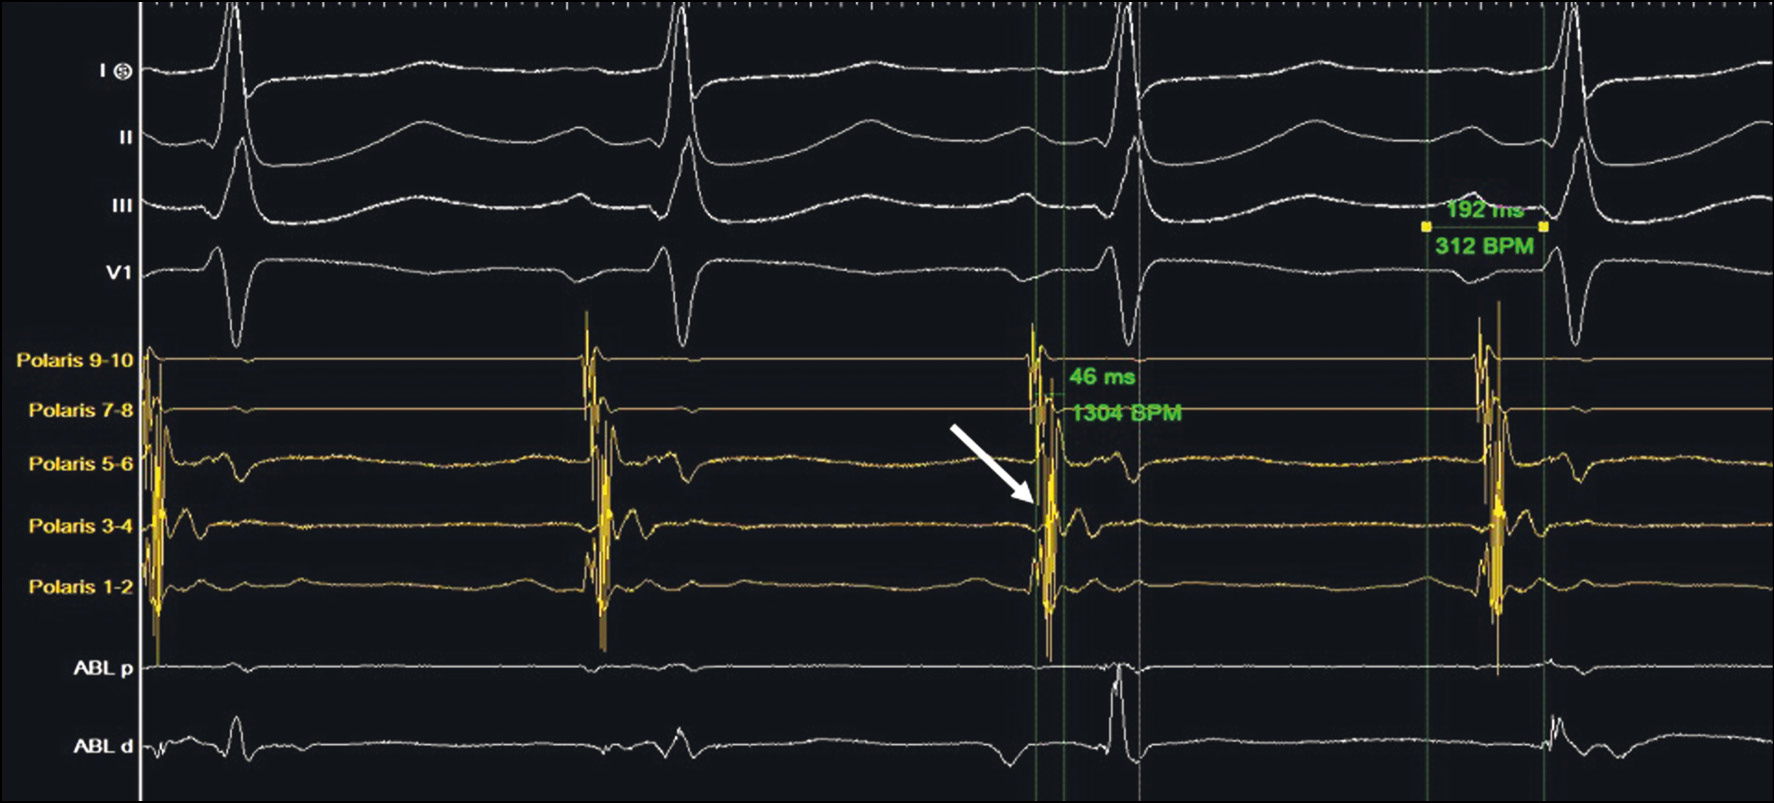

Через бедренный венозный доступ позиционированы электрофизиологические диагностические катетеры: 4-полюсный катетер в верхушке правого желудочка; 10-полюсный — в коронарном синусе. Выполнено электрофизиологическое исследование: исходно синусовый ритм с частотой сердечных сокращений 80/мин, PQ 192 мс, QRS 98 мс. Признаки предвозбуждения желудочков не регистрируются. Выполнена асинхронная и программированная антеградная стимуляция из предсердия: базовая частота стимуляции 500 мс. Антеградный эффективный рефрактерный период атириовентрикулярного соединения 240 мс. Антеградная точка Венкебаха 360 мс. При проведении асинхронной и программированной ретроградной стимуляции определяется эффективный рефрактерный период ДАВС 320 мс, ретроградный эффективный рефрактерный период атириовентрикулярного соединения 220 мс. На эндограмме с катетера коронарного синуса определяется сближение предсердного и желудочкового потенциала слева (рис. 4).

Рис. 4. Этап дооперационного электрофизиологического исследования: определяется сближение предсердного и желудочкового потенциалов менее 50 мсек в области левых полюсов диагностического катетера из коронарного синуса (указано стрелкой).

Fig. 4. Pre-operative electrophysiology study. One can see the atrial and ventricular potentials getting closer (<50 msec) in the region of the left poles of the diagnostic catheter from the coronary sinus (marked with an arrow).

Выполнен доступ в левое предсердие посредством пункции межпредсердной перегородки, в левое предсердие проведен ирригационный радиочастотный абляционный катетер и позиционирован в проекции левого бокового ДАВС. После получения удовлетворительных электрофизиологических параметров (раннее опережение на абляционном катетере, соотношение предсердного и желудочкового спайков в соотношении 1:3) выполнено 10 радиочастотных аппликаций по 60 сек каждая, энергией 45 Вт и температурой 45°С, параметры ирригации катетера — 30 мл/мин. При проведении контрольного электрофизиологического исследования данных за функционирование ДПЖС нет (рис. 5), антеградная точка Венкебаха 360 мс. Наблюдение — 30 мин с последующим контролем электрофизиологических параметров.

Рис. 5. Послеоперационное электрофизиологическое исследование: определяется центральный тип активации проводящей системы без признаков предсердного-желудочкового соединения (указано стрелкой).

Fig. 5. Post-operative electrophysiology study. One can see the central type of the conducting system, without signs of an atrioventricular connection (marked with an arrow).